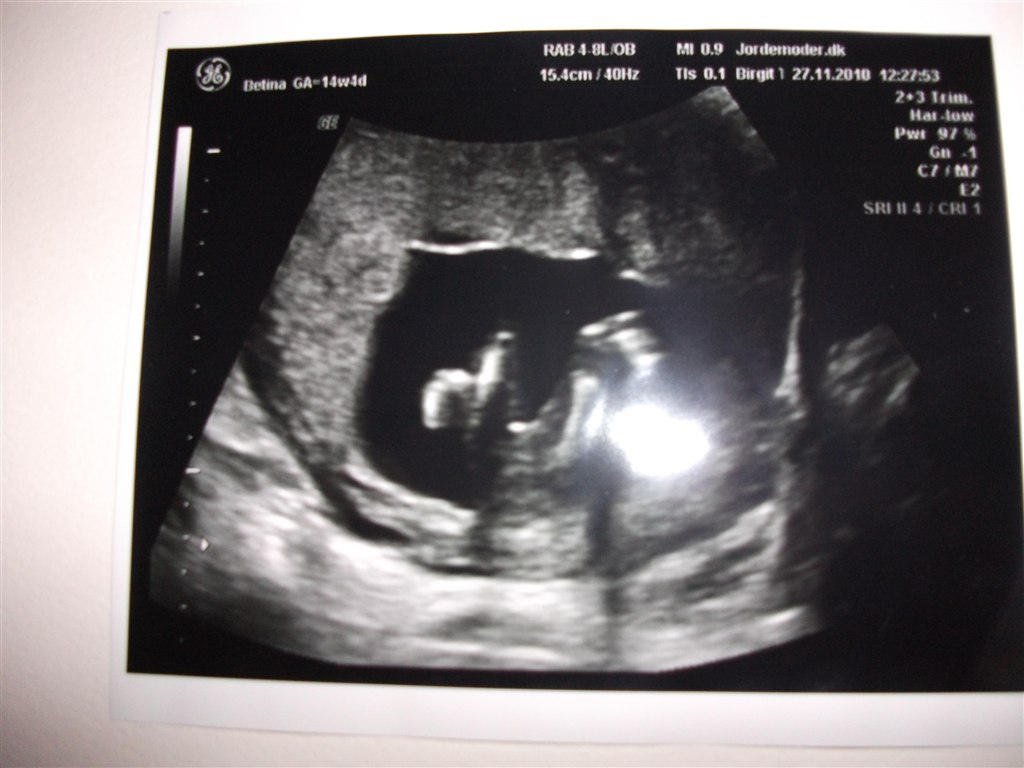

fik taget billeder nedefra så man kunne se kønsdelen, prøver lige at ligge det ind så i kan se det.. for der er slet ingen tap.

barnet ses med benene ud til siden og det lyse flade mit på skulle vise kønnet.